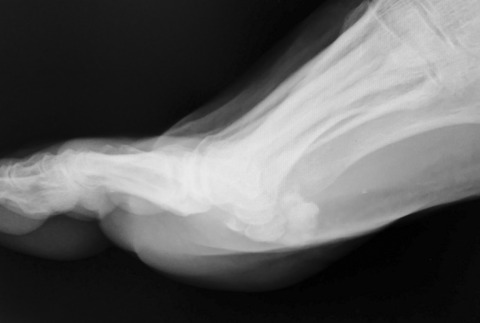

足部の側面像を撮影して、確定診断にいたりました。長母趾屈筋腱に発生した石灰沈着性腱炎です。う~ん、痛風発作と非常に紛らわしい。

しかし、これを誤診してしまうと、長期間に渡る高尿酸血症の治療を開始してしまう危険性があります。たまたま気付いてラッキーでした。。。